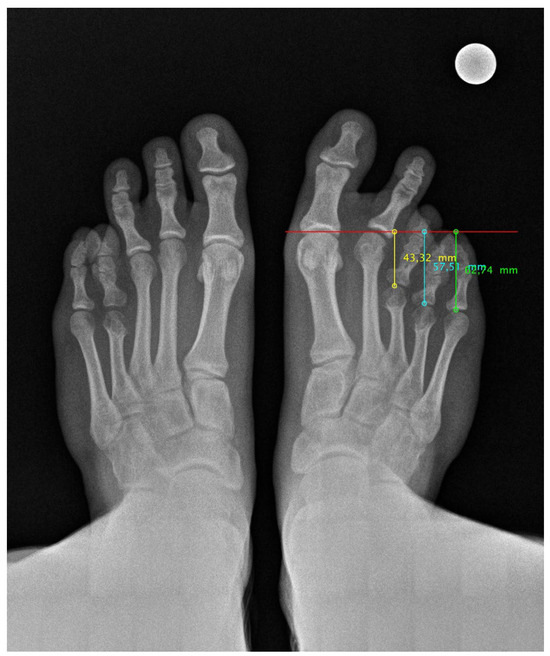

Anteroposterior and lateral radiographs were taken at 6, 12, 18, and 24 months post surgery (Figure 3). The radiological study shows correct bone consolidation, good alignment of the metatarsal parabola, as well as the remodelling process of the calcaneus following autograft removal. However, a painless non-union of the fifth metatarsal osteotomy is observed, which remains asymptomatic and does not interfere with the patient’s functionality.

Figure 3. Radiological image 24 months post surgery of both feet in loading. Improvement of the metatarsal parabola harmony can be seen.